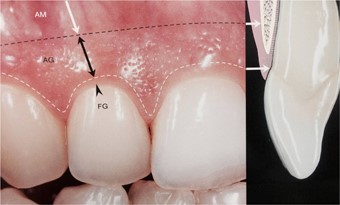

口元の美しさには「歯茎」も大きく影響します。当院では、歯茎の生物学的な幅に配慮し、適切にフィットする高品質な被せ物を提供しています。

当院では、このガミースマイルに対する治療も行っています。具体的には、歯間長延長術と呼ばれる術式です。歯の見える部分(歯冠)を長く見えるように、歯肉を切除し、必要に応じて歯を支える骨を削ります。ガミースマイルでお悩みの方はぜひ一度、当院へご相談ください。